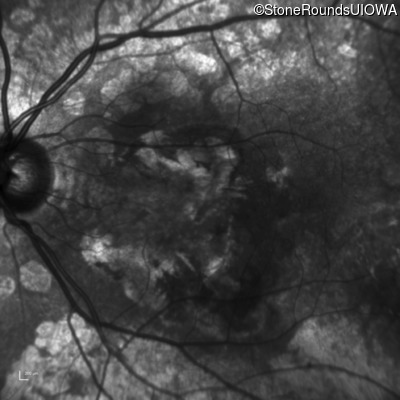

Age at visit: 64 years

This 64 year old woman first noticed some distortion in her vision at age 46 while looking at graph paper.

Age at visit: 66 years

Age at visit: 70 years